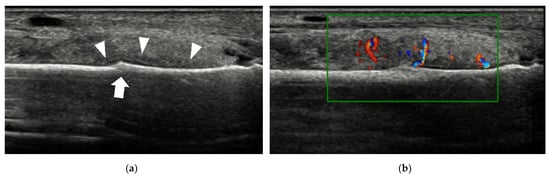

4.1.1. Plantar Plate Tear

| Plantar plate tear | 2nd MTP joint | discrete anechoic cleft or area of heterogeneous echotexture in the plantar plate |